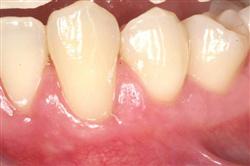

Normally gum tissue surrounds and protects the delicate roots of your teeth. Exposed tooth roots are prone to tooth decay, root canals, discoloration and actual jawbone loss. All of this can lead to tooth loss in advanced cases.

Functional Soft Tissue Grafting replaces the missing gum tissue and protects your teeth. For this reason, soft tissue grafting may be recommended even for back teeth.